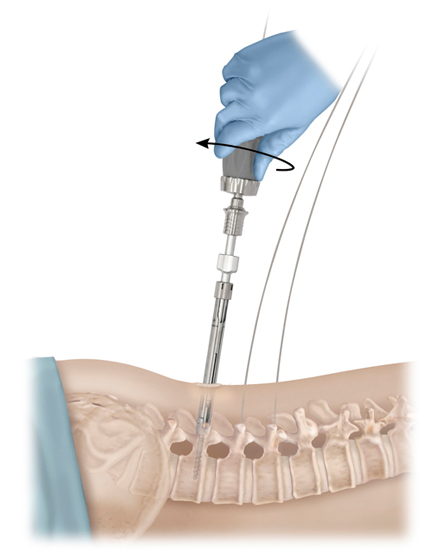

低侵襲脊椎側方固定術 XLIF (エックスリフ)、OLIF(オーリフ)

適応となる疾患:腰椎椎間板ヘルニア、腰部脊柱管狭窄症、腰椎変性すべり症、腰椎変性側弯症など

日本では2013年から承認されている低侵襲な脊椎側方固定術です。この手術は、トレーニングを受けた医師だけが実施できるため、全国でも限られた医療機関でのみ受けられます。当センターの日方医師は資格を有しているため実施可能です。この手術の最大の利点は脊髄神経を直接触らないで神経を圧迫から解除することにあります。側腹部に約5cmの皮膚切開により、下図のように神経機能を電気モニタリングで随時確認し重要な神経を避けながら椎間板内に人工骨を移植します。その後、腰部から固定術を行います。翌日から起立・歩行が許可され、入院期間は通常10~14日程度になります。